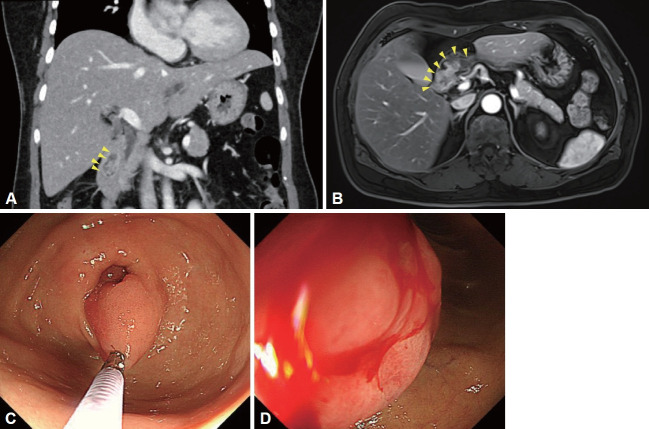

Duodenal Mass Detected on the Screening Endoscopy.